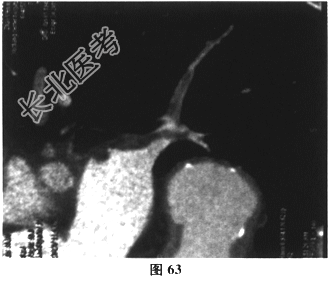

- 多项选择题3.[提示]入院后持续监测,生命体征平稳, 经对症治疗症状逐渐缓解。进一步检查,下肢深静脉多普勒超声: 右侧腘静脉、胫后静脉多发血栓形成。肺动脉CTA(图62~图65)示双肺动脉分支多发栓塞。冠脉CTA示冠脉多处钙化斑块,前降支中段轻度狭窄。BNP36.8pg/ml(正常0~100pg/ml)。TNI<0.05ng/ml(正常0~0.4ng/ml)。动脉血气分析: 氧分压63mmHg,二氧化碳分压28.7mmHg。